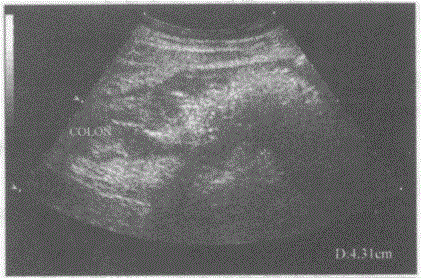

问题 临床资料:男,62岁,自述右下腹痛,便血。 化验检查:便潜血阳性。 超声综合描述:右下腹扫查升结肠起始段可见假肾样回声区,肠壁不均匀增厚,厚度0.81.2cm。 超声提示:

选项 A.结肠正常声像图 B.结肠炎 C.阑尾炎 D.结肠癌

答案 D